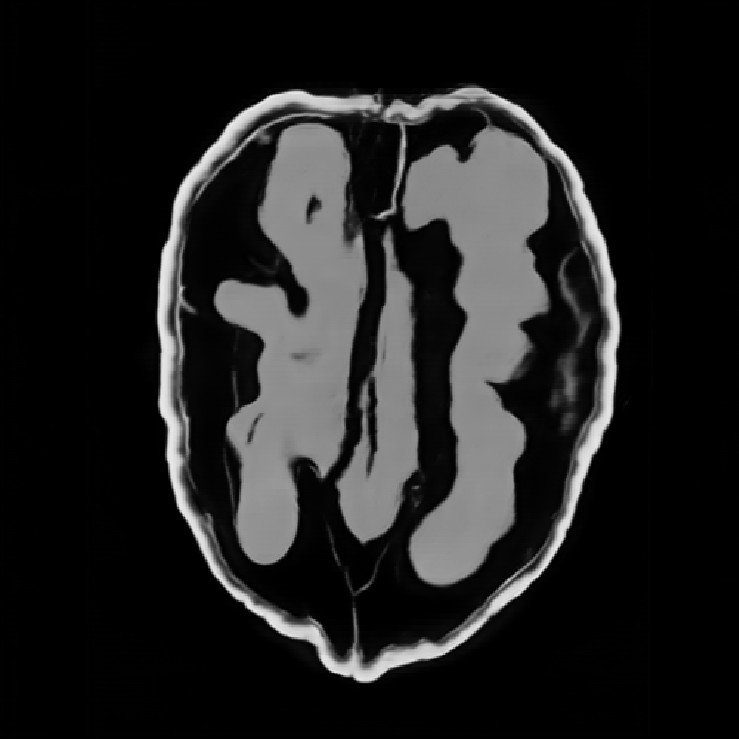

In this work, we find that a good approximation of the normal operator can be obtained by factorizing it as the product of a diagonal matrix and a circulant matrix, which can be efficiently applied using FFTs. This allows us to significantly reduce the computational cost of the data-fidelity step, while maintaining good reconstruction performance. \begin{equation} \label{eq:normal:operator:approximation} \mA^\top \mA \approx \mH = \mathrm{diag}(\vm)^* \mF^{-1} \mathrm{diag}(\bm{\lambda}) \mF \mathrm{diag}(\vm), \end{equation} where $\mF$ and $\mF^{-1}$ are the Fourier and inverse Fourier transforms, respectively, $\vm \in \R^{n}$ is homogeneous to spatial sensitivity map, and $\bm{\lambda} \in \mathbb{C}^{n}$ is the frequency response of the convolution kernel associated with $\mA^\top \mA$.

The parameters $\vm$ and $\bm{\lambda}$ can be learned end-to-end by minimizing the loss \begin{align} \mathcal{L}(\vm, \bm{\lambda}) &= \E_{\rvx \sim \mathcal{N}(\bm{0}, \mI)} \| \mA^\top \mA \rvx - \mH(\vm, \bm{\lambda}) \rvx \|_2^2 \notag\\ &= \| \mA^\top \mA - \mH(\vm, \bm{\lambda}) \|_F^2 \label{eq:frobenius:loss} \end{align}

Illustrations of the normal operator approximation on the Walnut-CBCT dataset. (top row) Original volume slice $\vx$, exact normal operator evaluation $\mA^\top \mA \vx$, and approximated normal operator $\mH\vx$. (bottom row) Learned filter $\bm{\lambda}$, learned mask $\vm$, and squared approximation error $(\mA^\top \mA \vx - \mH \vx)^2$.

Now we can use the approximation $\mH$ instead of the exact normal operator $\mA^\top \mA$ in the partitioned data-fidelity step \eqref{eq:data:step:partitioned}. The factorization $\mH$ admits an efficient evaluation on a small patch by restricting the size of underlying convolution kernel, and by cropping the spatial mask $\vm$ to the patch size.